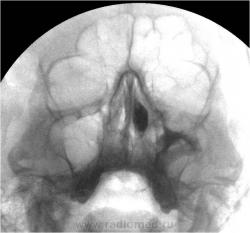

Гайморография

Вашему вниманию представляется несколько случаев контрастной гайморографии...Ваше мнение?...продолжение следует...

Публикации: 7066

ГАЙМОРОГРАФИЯ (гайморо- + греч. grapho писать, изображать; син. максиллография) – рентгенологическое исследование верхнечелюстных синусов после введения в них контрастного вещества путем прокола ее стенки, через лунку удаленного зуба (при наличии сообщения с синусом) или через свищевой ход. После аспирации содержимого пазухи вводят 3-7 мл слегка подогретого контраста (йодолипол, йодипин, липийодол и др.). Снимки выполняют в носо-подбородочной и боковой проекциях. Методика показана для диагностики кист, полипов пазух, продуктивных форм гайморита, опухолевых заболеваний.